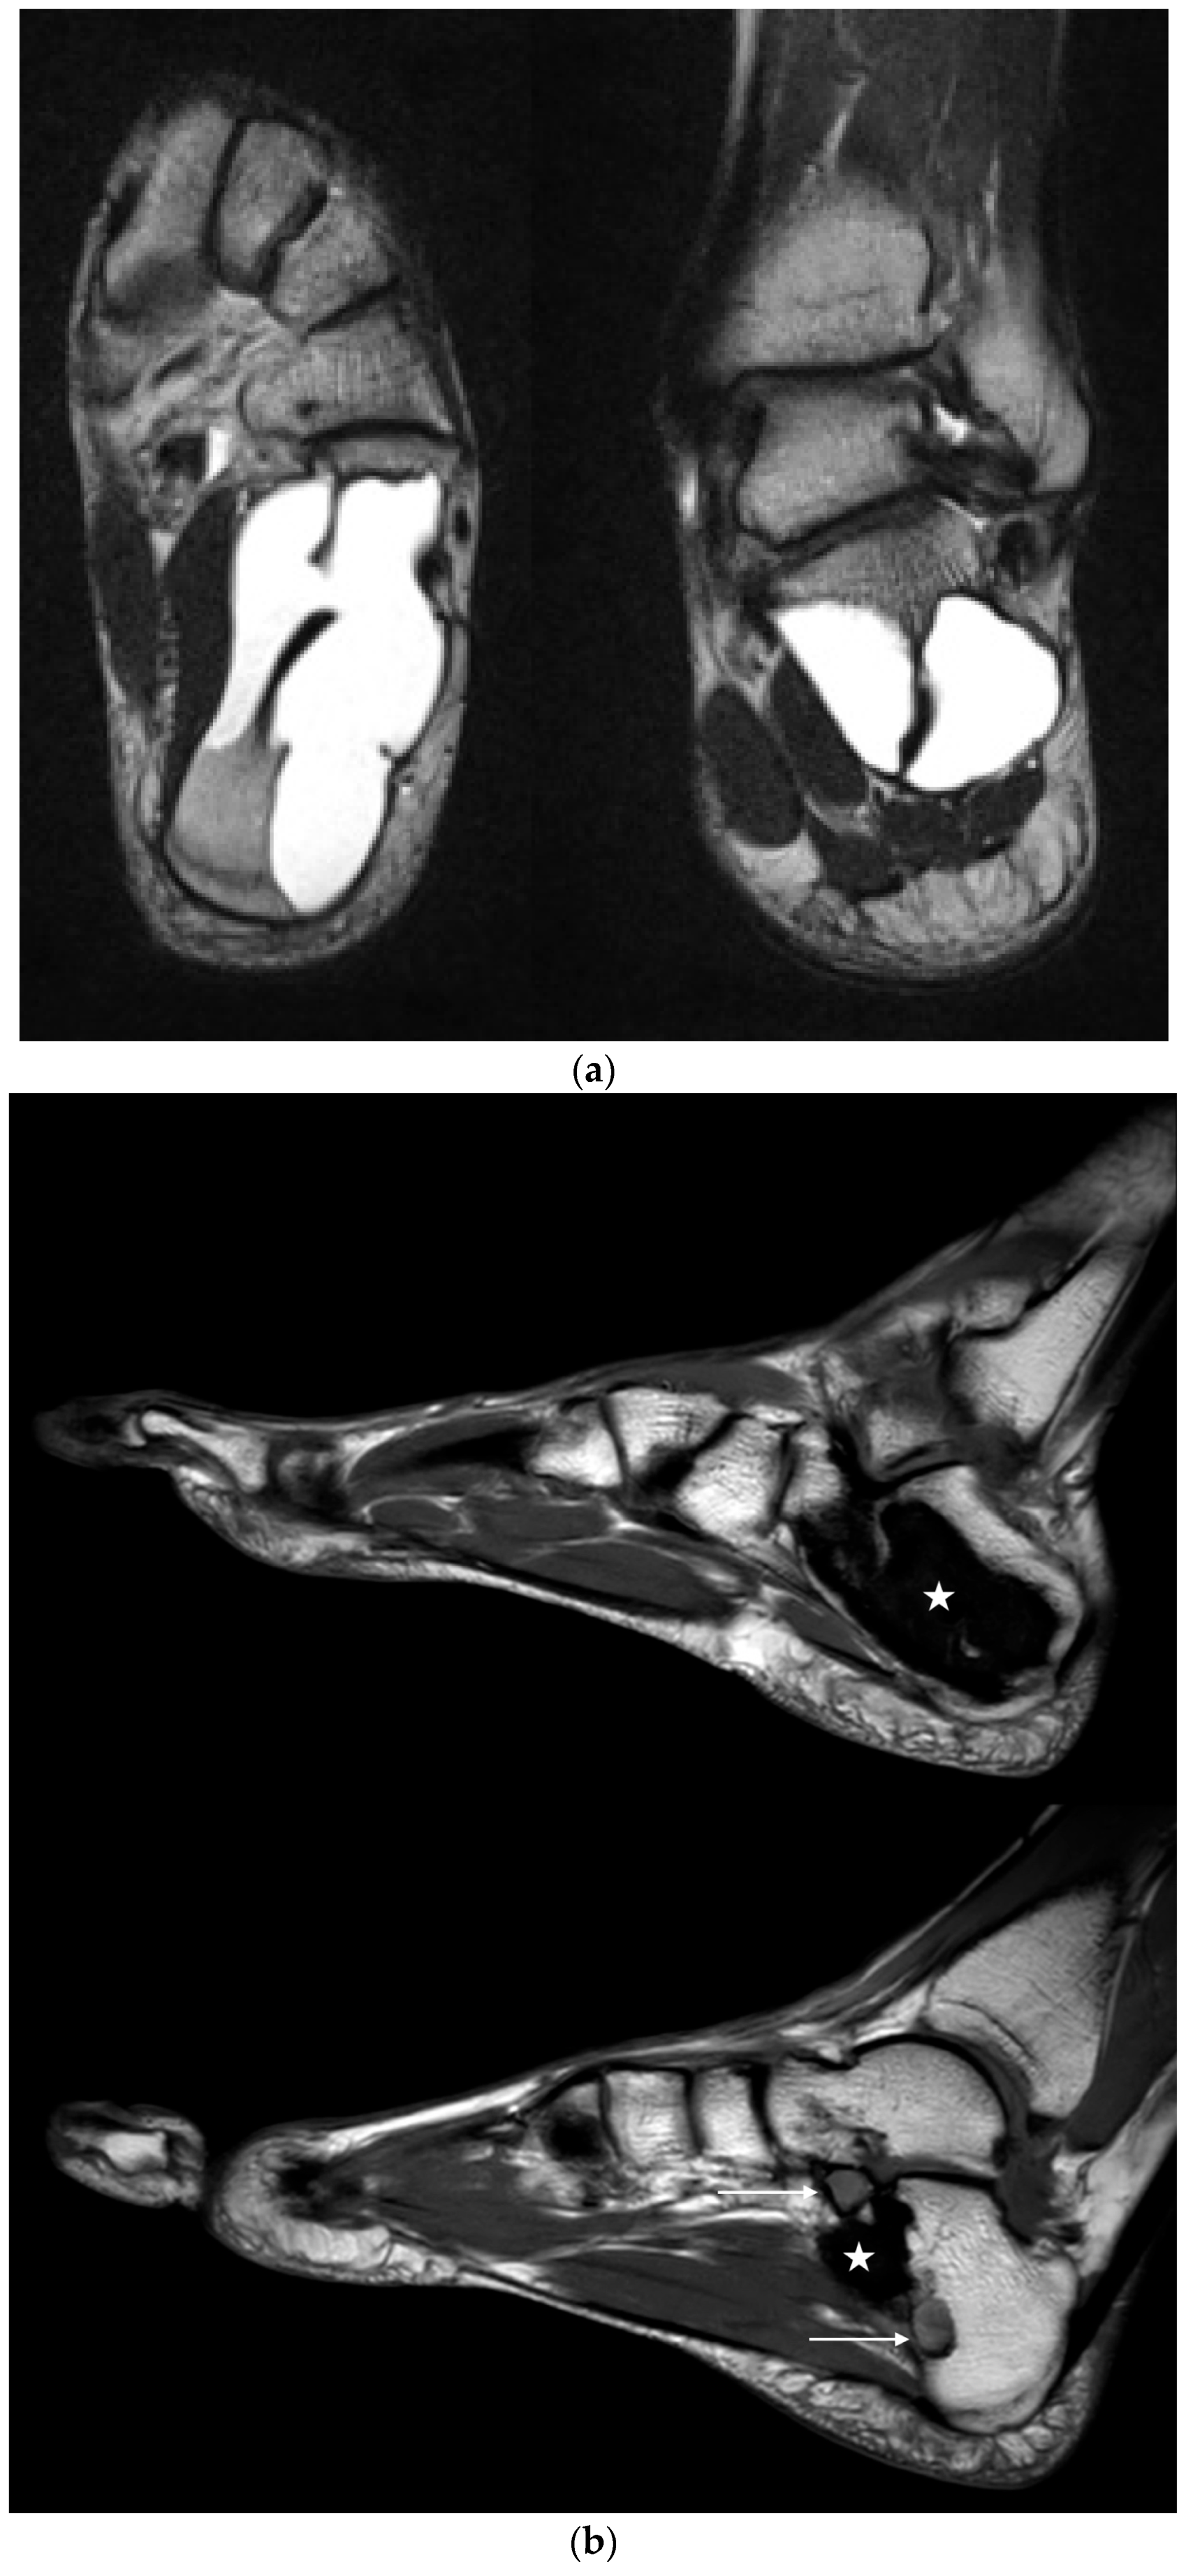

Figure 6.

(a) Axial and coronal T2 TSE-weighted MRI showing a large SBC in a 31-year-old professional ballet dancer (case 6). After endoscopic resection, the bone cavity was filled with injectable bone substitute. (b) Sagittal T1-weighted MRI performed 91 months postop, showing two small areas of recurrence of SBC at the medial aspect (bottom image, arrows). The large cyst cavity was filled with QuickSet© injectable bone substitute (marked with a star), showing no signs of osseous remodeling more than 7.5 years after implantation. The patient is currently free of symptoms and still performs at the highest level of professional ballet dancing.